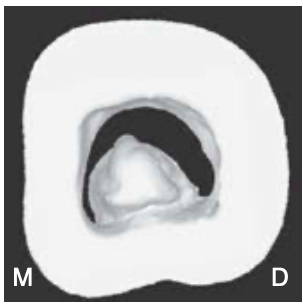

type I of pulpal floors

a peninsula-like floor with continuous C-shaped orifice

type II of pulpal floors

A buccal, striplike dentin connection between the peninsula-like floor and the buccal wall of the pulp chamber that separates the C-shaped groove into mesial (M) and distal (D) orifices.

Sometimes the mesial orifice is separated into a mesiobuccal (MB) orifice and a mesio- lingual (ML) orifice by another striplike dentin connec- tion between the peninsula-like floor and the mesial wall of the pulp chamber (most common)